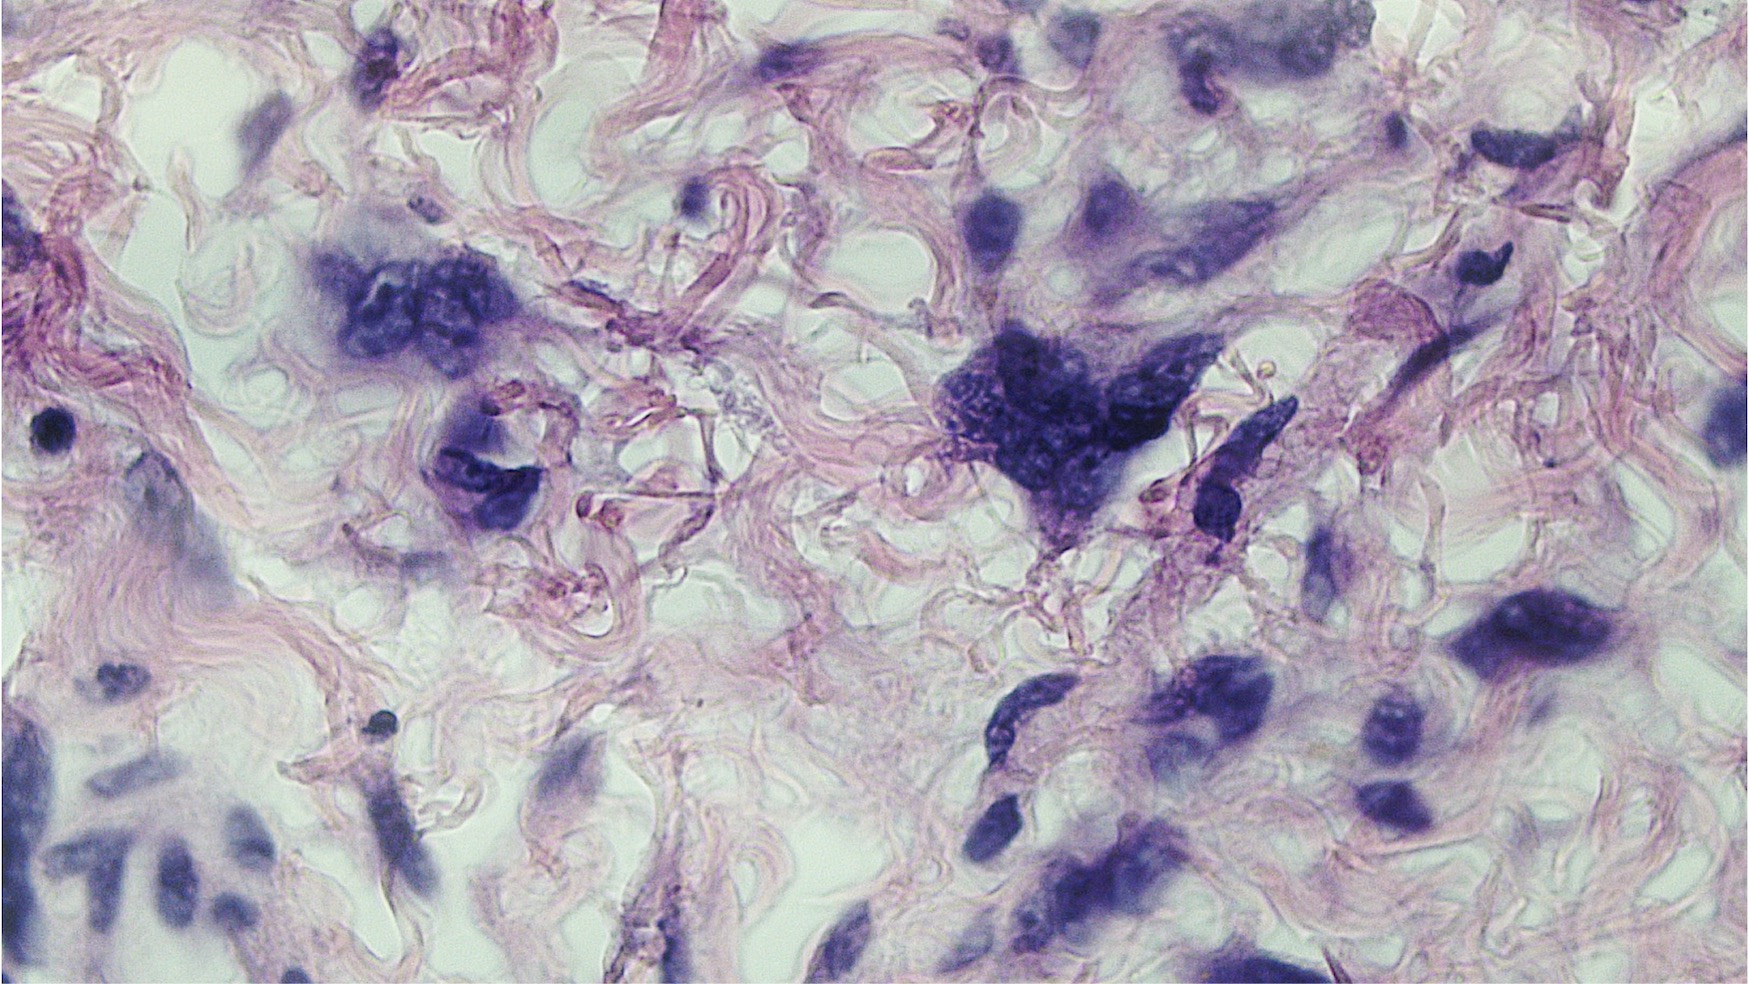

Microscopic (histologic) description

- Polypoid and noncircumscribed, extending to the epithelial / subepithelial interface (J Low Genit Tract Dis 2011;15:69, Am J Surg Pathol 2000;24:231)

- 2 stromal cellularity variants: hypocellular form (spindle cells set within a loose collagenous myxoid-like stroma) or hypercellular variant (exhibits marked nuclear pleomorphism and frequent mitoses, including atypical forms), especially during pregnancy, therefore mimicking leiomyosarcoma or rhabdomyosarcoma (Am J Surg Pathol 2000;24:231)

- Stellate cells should not be interpreted as sarcoma (J Low Genit Tract Dis 2011;15:134)

- Commonly found around blood vessels or near the epidermal stromal interface

Microscopic (histologic) images